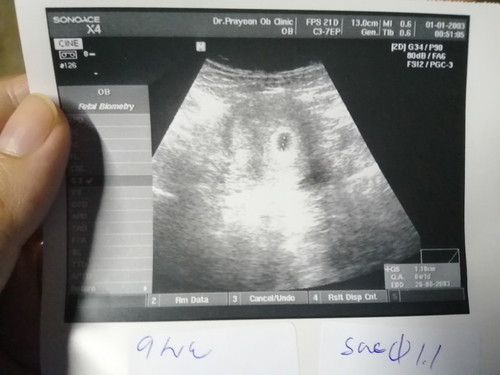

ท้อง 6week ขนาดตัว 1.1 cm นี้ถือว่าปกติไหมคะ หรือเล็กไป